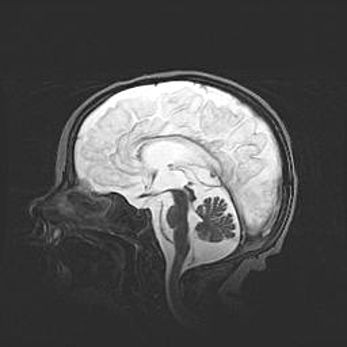

Неполная лизэнцефалия (пахигирия). Открытая гидроцефалия.

Возраст: 17 дней

Вес: 3110 г

Пол: мужской

Окружность головы: 33,5 см

Срок гестации: 35-36 недель

Лизэнцефалия—недоразвитие корковой пластинки и мозговых извилин в результате нарушения миграции нейронов коры. Поверхность мозговых полушарий гладкая. Микроскопически выявляется отсутствие нормальных слоев коры и скопление групп нейронов в подкорковом белом веществе.

Пахигирия—уменьшение числа вторичных извилин. В пораженном полушарии нервные клетки образуют толстый недифференцированный слой с неправильно расположенными нервными волокнами и группами гетеротопных клеток. Нервные клетки незрелые. Белое вещество истончено. При этом нередко аномально развит корково-спинномозговой путь.